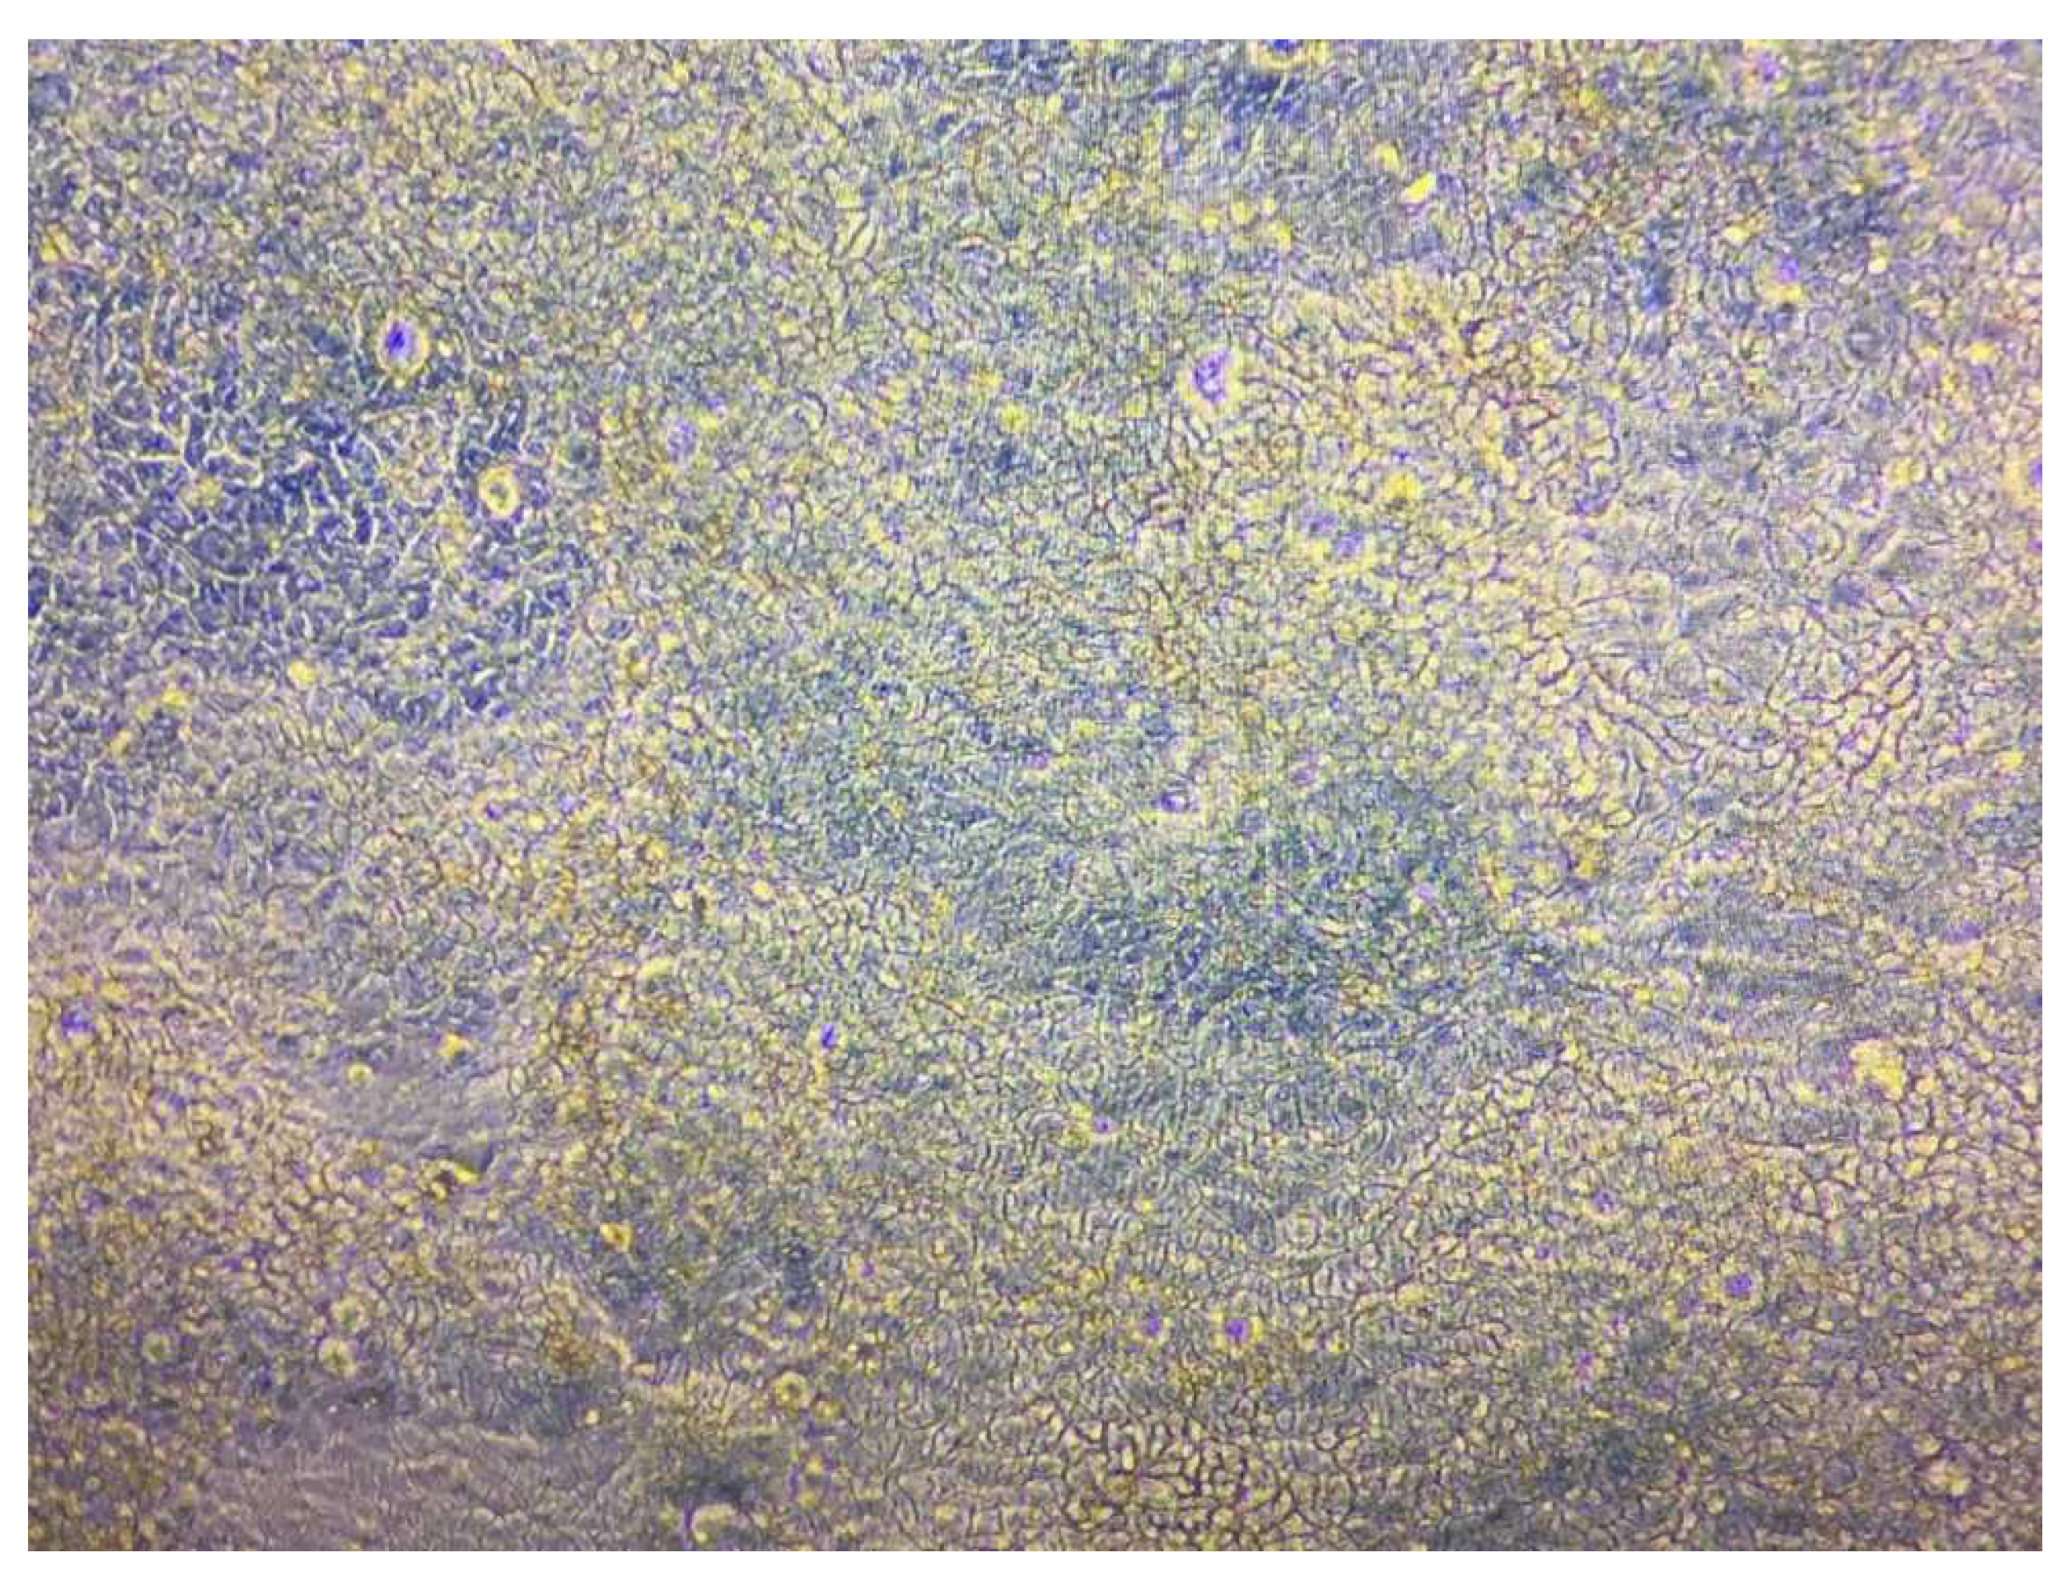

3.9. Cellular Uptake Study

4.9. Cellular Uptake Test